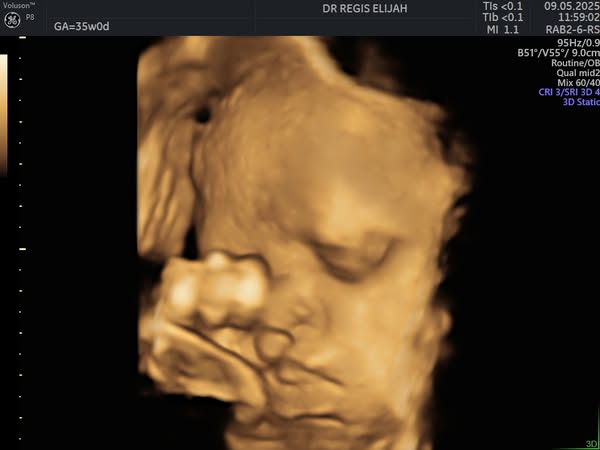

There’s nothing more magical than seeing your baby for the first time—and with our advanced 4D ultrasound technology, you don’t have to wait until delivery day to witness those precious moments!

At Elijah R OBGYN Women’s Clinic, our 4D pregnancy scans allow expectant parents to view their baby’s movements, facial expressions, and little kicks in real time, creating a powerful bonding experience.

🔸 Capture beautiful real-time images

🔸 Detect and monitor fetal development